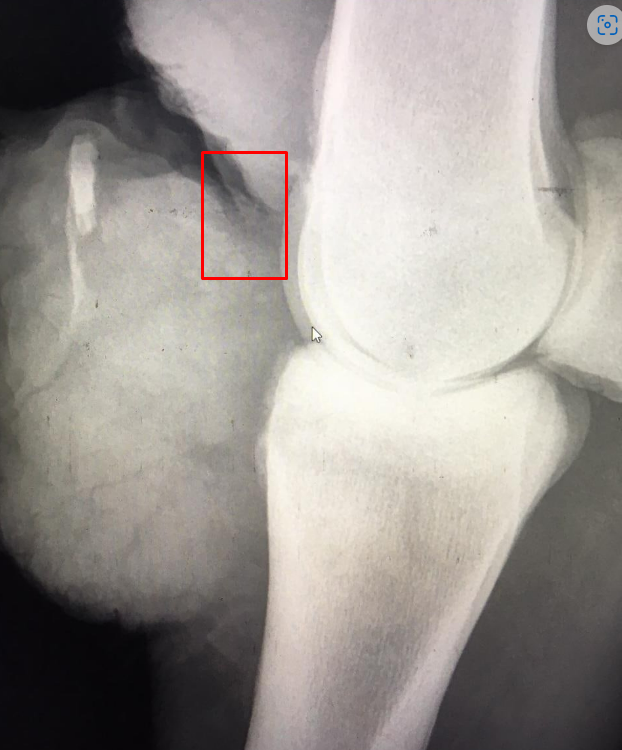

Я дико извиняюсь, а что именно на вашем снимке указывает на несовместимость с жизнь?

Человек не понимает что видит на рентгене. Он считает, что затемнение - это "разрыв суставной сумки". Хотя мне больше думается, что это граница разрыва дикого мяса (или что там уже наросло), которое "светится".

Это не мое мнение, это мнение квалифицированных врачей. И оно звучит не так. Я считаю что снимок моего рентгена характеризует рваную рану на снимке продавца, при ранении, с разницей, отека и разрастания тканей, а то, что поналечила врач продавца, такого не бывает, без вмешательства

нарушения в суставе видны

Я серьезных не вижу, но зато я видела рентгены артритов на поздних стадиях. У вас и близко такого нет. То из-за чего у вас лошадь пытается умереть на рентгене не видно.

В вашем случае, как я поняла из ваших спутанных объяснений, опасно не повреждение сустава и не артрит, а сепсис, который мог начаться из-за загноения. Но это не то, что видно на рентгене.

Поэтому я уже которую страницу упорно не могу понять, с какой целью топикстартер упорно всем тычет рентгеновскими снимками в случае повреждения мягких тканей.

Потому что ей прислали снимки в доказательство того, что кости целы. А дальше по поговорке - были бы кости - мясо нарастёт.

Справедливости ради, эта травма не является травмой несовместимой с жизнью, но транспортировать таких лошадей в таком состоянии, особенно на большие расстояния нельзя - именно перевозка дала угрозу жизни этой лошади (угроза сепсиса). Т.е. продавец не имела права продавать эту лошадь, тем более с перевозкой на большие расстояния, не пролечив ногу. Там что получилось - после травмы лошадь обработали и поставили без движения. Обработали недостаточно хорошо - осталась инфекция внутри. Далее снаружи рана затянулась, а внутри стал развиваться гнойный абсцесс. После того, как лошади пришлось этой ногой активно двигать при перевозке - всё то, что наросло и внешне выглядело ровненько - лопнуло и потекло. Кстати это хорошо, что лопну и потекло, если бы осталось бы внутри - было бы хуже.